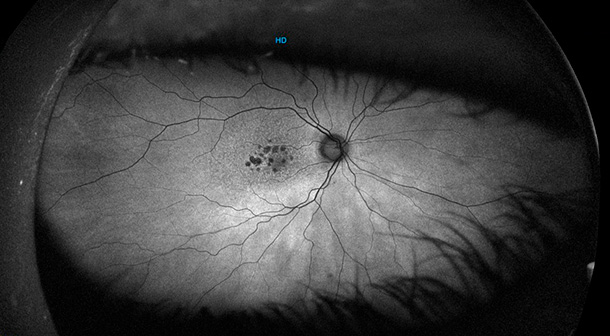

La DMAE afecta la parte central de la retina, donde se encuentra la visión central y se produce la fijación. Su conservación tiene un alto valor, ya que nos permite llevar a cabo actividades diarias y simples como leer, ver la televisión o conducir sin dificultad. Sus síntomas más comunes son experimentar visión central borrosa, o percibir una mancha en el campo visual.

También llamada DMAE seca. Es aquel tipo de DMAE sin líquido dentro de la retina. La pérdida es más lenta, pero al igual que la DMAE húmeda es también irreversible.

Se ha detectado que las drusas, que son unos depósitos que aparecen debajo de la retina en pacientes con formas iniciales de DMAE, están llenas de proteínas del sistema del complemento. También se ha detectado que mutaciones genéticas en este sistema del complemento se han asociado con un riesgo mayor de desarrollar DMAE. De ahí la convicción de que el sistema inmune participa, aunque solo sea en parte, en la génesis de la DMAE.